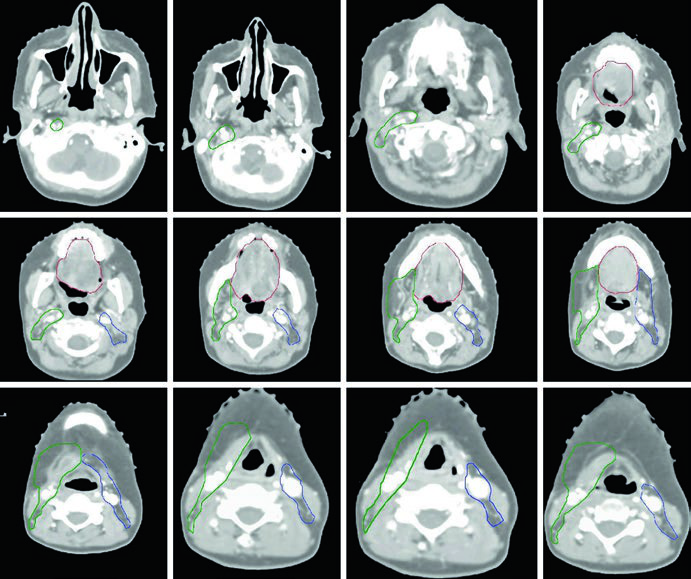

Caso Clínico: Carcinoma de Lengua Oral T3N2b

La Figura 6.1 ilustra un paciente con carcinoma espinocelular (CEC) de lengua oral, estadio patológico T3N2b, post-glosectomía parcial con márgenes quirúrgicos microscópicamente positivos. El CTV66 (rojo) cubre la región del margen positivo. El CTV60 (verde) abarca todo el lecho quirúrgico, y el CTV54 (azul) incluye los niveles ganglionares cervicales.

En el lado ipsilateral se incluyen los niveles I a V. En el contralateral sin enfermedad, niveles I a IV. La cobertura del nivel V se recomienda para tumores primarios de lengua oral, especialmente tras manipulación quirúrgica del cuello y en presencia de enfermedad ganglionar ipsilateral. El nivel IA debe cubrirse sistemáticamente.

Cuando existe preocupación por compromiso de tejidos blandos superficiales, se recomiendan bolus y flash. El espacio retroestiloideo ipsilateral es zona de riesgo para metástasis ganglionar, particularmente con compromiso del nivel II. Los ganglios retrofaríngeos presentan bajo riesgo y generalmente no se incluyen. La cobertura del nivel VI se recomienda enfáticamente en pacientes con enfermedad ganglionar positiva.